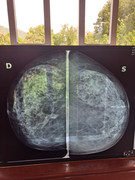

Ora posto la mammografia di mamma fatta a gennaio e nel referto si leggeva, sovrapponibile con quella dell anno precedente, con presenza di necrosi sotto cicatrice

Poi a giugno l ecografia riporta area ipoecogena di 8 mm

Non riesco a capirci nulla